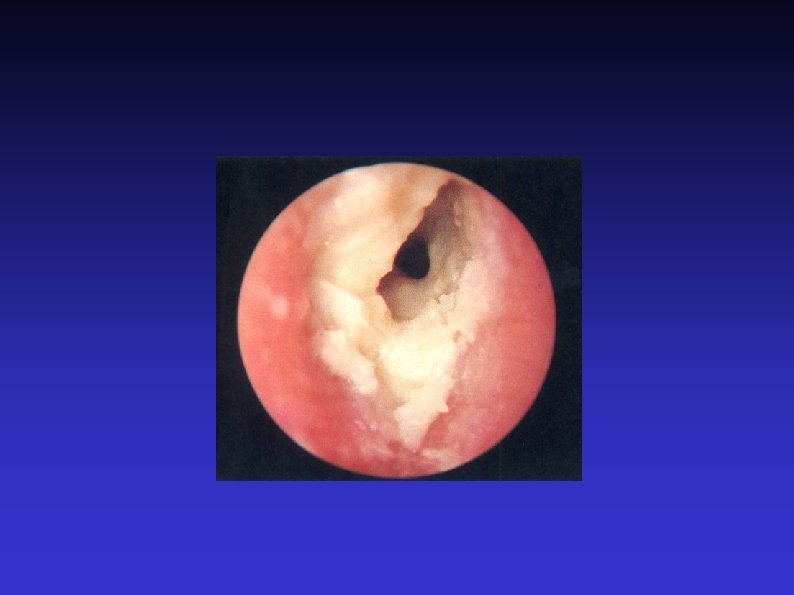

Examination of the Ear 7) Otoscopic examination The lateral process and handle of the malleus lie towards the centre of the tympanic membrane Four quadrants Perforation Central or marginal What can be seen through it Mastoid cavity Dry Wet, inflamed